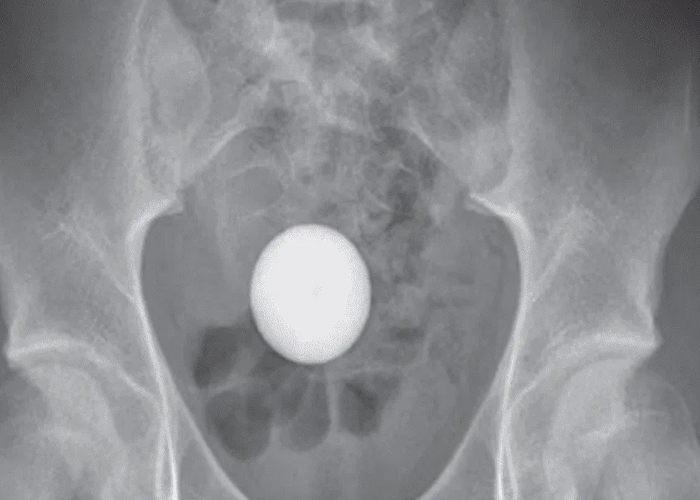

De acuerdo con la revista Case Reports in Surgery, en el hospital se le hicieron varios escaneos de rayos X, donde los médicos pudieron observar que el objeto, el cual era una pelota de golf había llegado hasta su colon sigmoide, la última parte del intestino grueso, que se conecta con el recto.